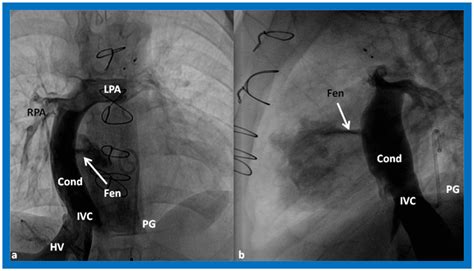

2. The Glenn Procedure (Bidirectional Glenn): Usually performed between 4 and 6 months of age, this connects the superior vena cava directly to the pulmonary arteries.

3. The Fontan Procedure: Typically performed between ages 2 and 5, this creates a final pathway for blood returning from the lower body to flow directly into the pulmonary arteries.